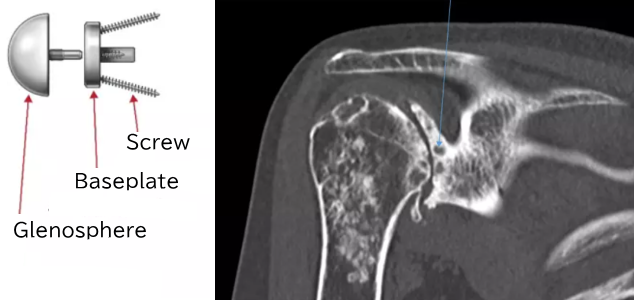

- In reverse shoulder arthroplasty as well, if the glenosphere (the implant placed in the glenoid) is not positioned optimally, there is a risk of loosening. This is because in cases of severe bone deformity, the amount of bone in the glenoid is often insufficient. As a result, the fixation of the glenosphere, which is secured to the glenoid with screws, may not be adequate.

Normally, the baseplate is fixed to the glenoid with screws.

If the glenoid is deformed, the shape of the baseplate may not fit the glenoid properly.

Therefore, a shaped allograft is attached to the baseplate to fit the deformed glenoid.

The baseplate with the allograft is fixed to the glenoid.

The glenosphere is attached.